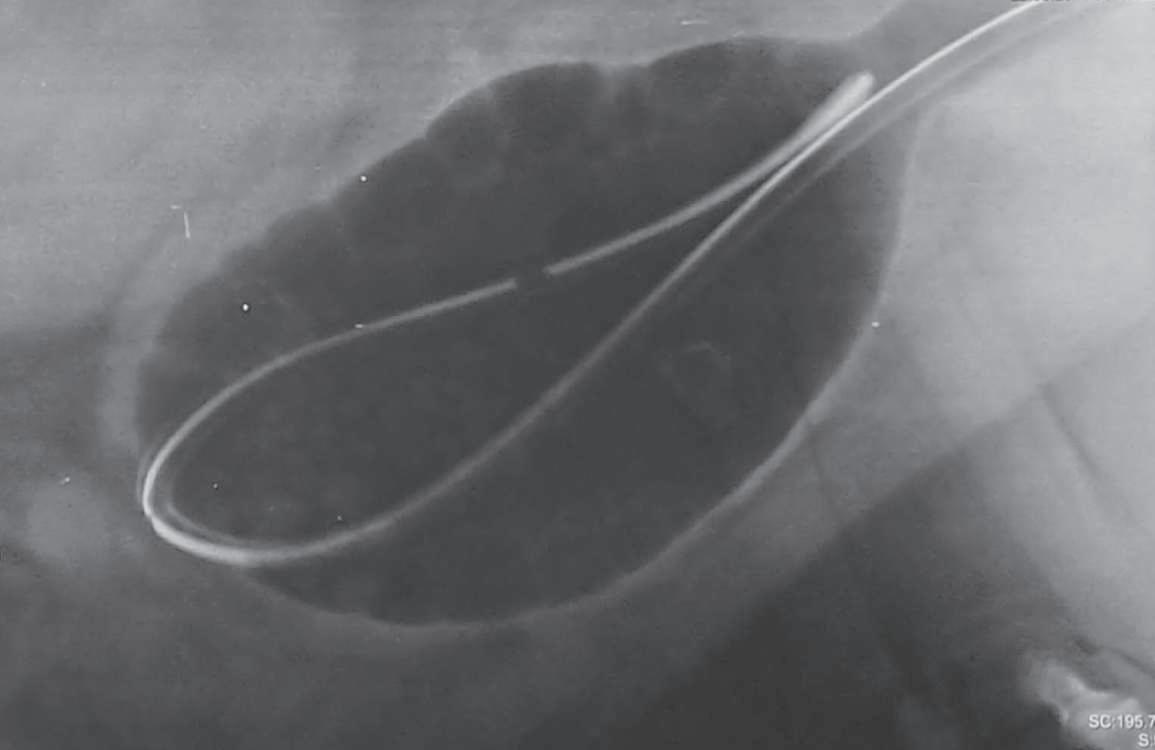

Imagen radiográfica en proyección lateral izquierda derecha, en la cual se aprecia vejiga plétora, con cambios de densidad en la luz vesical correspondientes a zonas aparentemente nodulares que corresponden a irregularidades en el contenido vesical como la presencia de urolitos (p. 81).